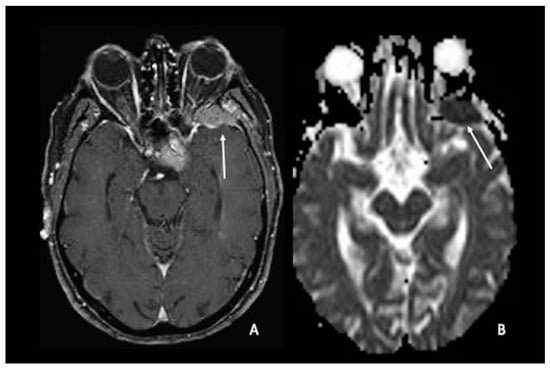

4. Lymphomas